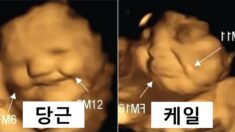

엄마가 단 걸 먹으면 웃고, 쓴 걸 먹으면 인상을 찌푸리는 뱃속 아기의 표정이 포착됐다. 지난 21일(현지 시간) 영국 더럼대학 공동 연구진은 엄마가 먹는 음식에 따라 태아가 ... 9월 30, 2022